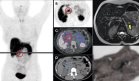

Una tomografía computarizada del cráneo reveló calcificaciones en la sustancia blanca periventricular y en la cisterna perimesencefálica.

Se realizaron estudios complementarios, incluyendo una densitometría ósea, que mostró una puntuación Z corregida por edad y sexo de -2,1 en la columna lumbar y el cuello del fémur, sugiriendo osteopenia. Las radiografías de la columna vertebral mostraron fracturas vertebrales en L3 y L4, características de fragilidad ósea, además de osteocondromas en el peroné y el antebrazo derecho, indicativos de un trastorno esquelético.